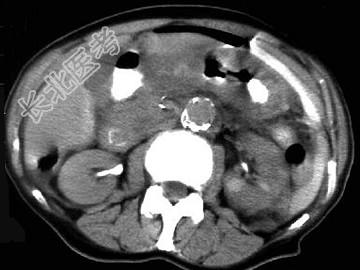

- 单项选择题男,44岁, 突然中上腹痛,压痛, 反跳痛,腹肌紧张, 发热,白细胞计数升高, CT检查如图,最可能的诊断是 ( )

A、急性胰腺炎

B、慢性胰腺炎

C、胃小弯溃疡穿孔

D、胰腺癌

E、胃癌